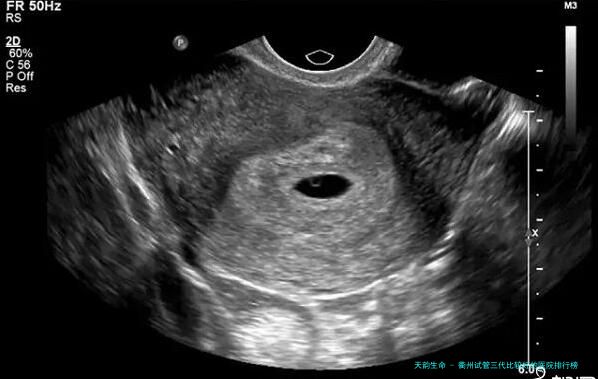

女性需做六种性激素,卵巢amh实践、子宫超音波检查等检查。

促排卵是将促排针注射到肚子里,大概要8-九天,每日1次。期间需将要去医院做超声诊断检查,察看卵泡发展情况。比及卵泡发育成熟,进行试管,同一时刻男方取精,进行胚胎培植。